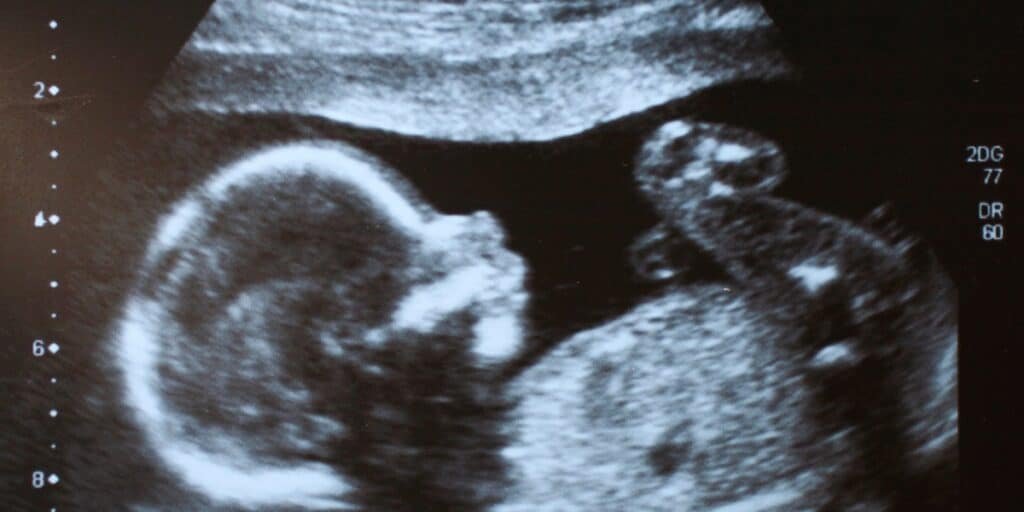

O avanço tecnológico permitiu facilitar, e muito, diversos processos, inclusive a gestação. A ultrassonografia tornou-se uma ferramenta indispensável no acompanhamento pré-natal, permitindo a visualização detalhada do desenvolvimento fetal em diferentes fases da gravidez.

Esse exame é fundamental para avaliar a saúde do bebê, identificar precocemente possíveis anomalias e fornecer informações importantes para a equipe médica. Além do aspecto clínico, a ultrassonografia também proporciona um momento especial para os pais, que podem acompanhar de perto o crescimento do bebê e fortalecer o vínculo afetivo antes mesmo do nascimento.

A ultrassonografia desempenha um papel essencial no acompanhamento da gestação, garantindo mais segurança tanto para a mãe quanto para o bebê. Esse exame permite avaliar o desenvolvimento fetal em cada trimestre, identificando possíveis anomalias estruturais ou funcionais e auxiliando na detecção precoce de complicações que podem exigir intervenções médicas.

Além disso, a ultrassonografia é uma ferramenta indispensável para monitorar a placenta, o líquido amniótico e a posição fetal, informações que são fundamentais para a condução do parto. O exame também possibilita o acompanhamento de doenças maternas pré-existentes ou que possam surgir durante a gravidez, permitindo um planejamento mais adequado dos cuidados necessários.

Por ser parte integrante do pré-natal, a realização da ultrassonografia contribui para uma gestação mais segura, promovendo um acompanhamento detalhado e personalizado conforme as necessidades de cada gestante.